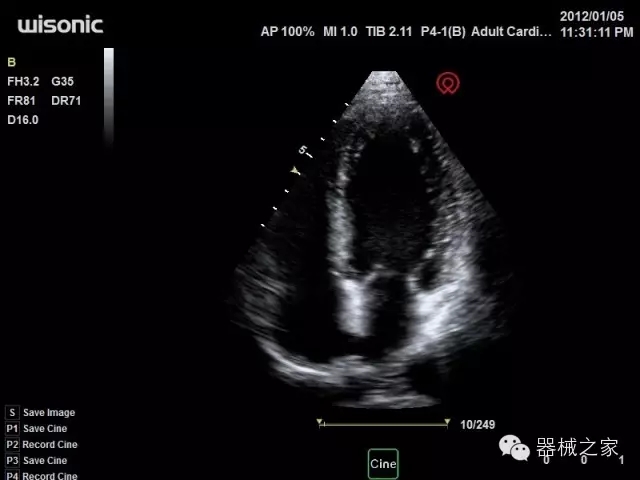

品牌:華聲醫(yī)療(WISONIC)

深圳華聲醫(yī)療技術(shù)有限公司成立于2012年,位于深圳南山西麗湖畔。是一家從事醫(yī)療設(shè)備研發(fā)、制造、營銷的新興高新技術(shù)企業(yè),目前提供生命信息支持、數(shù)字便攜彩超、移動(dòng)醫(yī)療服務(wù)三個(gè)方面的業(yè)務(wù)解決方案。公司核心創(chuàng)始人均為醫(yī)療設(shè)備行業(yè)領(lǐng)軍人物,在醫(yī)療行業(yè)服務(wù)時(shí)間平均在10年以上,對行業(yè)和產(chǎn)品積累了深刻的認(rèn)識。公司在創(chuàng)立之初就有著長遠(yuǎn)的戰(zhàn)略目標(biāo)和規(guī)劃,致力于醫(yī)療設(shè)備行業(yè)的細(xì)分市場,貼近客戶所需,為大眾的健康提供更多關(guān)愛。

官方網(wǎng)站:www.wisonic.cn

經(jīng)典產(chǎn)品:四葉草

臨床圖片賞析

產(chǎn)品特點(diǎn)

·全球目前唯一一款配備主機(jī)雙探頭接口,整機(jī)重量(含電池)在5公斤以內(nèi)的便攜式彩超;